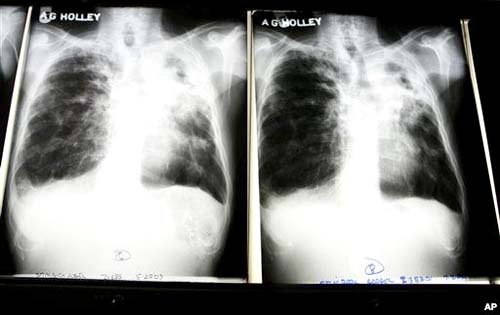

Hình ảnh X quang của một bệnh nhân bị lao phổi ở Bệnh viên A.G Holley, Lantana, Florida tháng 12 năm 2009 |